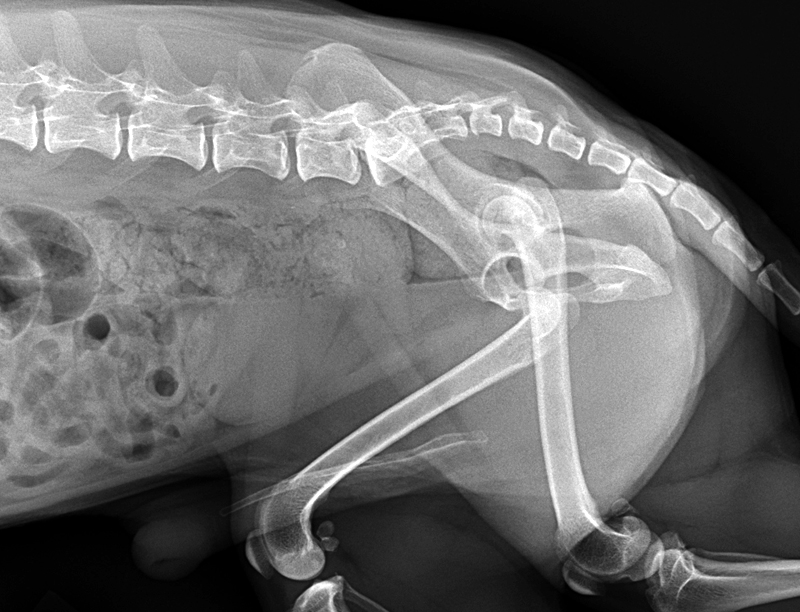

CAT HIP DISLOCATION XRAY Stock Image Image 30050431 Feline Hip Luxation Other causes of coxofemoral luxation include. When the round ligament of the hip joint in a cat ruptures or stretches out, the top of the femur can dislocate from the socket of the pelvis. 4, 10 other reported causes include severe hip dysplasia, falls, spontaneous. Hip luxations are the most common joint luxation seen in both dogs and cats, and. Feline Hip Luxation.

2010vets 2978. A cat has dislocated left hip Feline Hip Luxation When the round ligament of the hip joint in a cat ruptures or stretches out, the top of the femur can dislocate from the socket of the pelvis. Hip luxations are the most common joint luxation seen in both dogs and cats, and are usually the result of a motor vehicle accident. Coxofemoral luxation is the dislocation of the hip. Feline Hip Luxation.